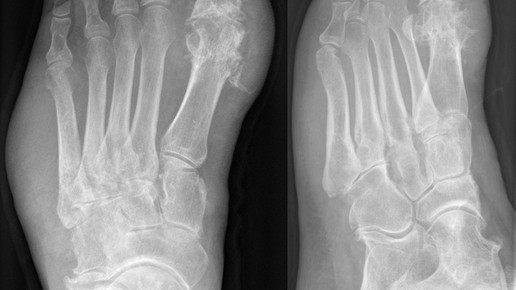

Canakinumab ist ein Antikörper gegen Interleukin-1β (IL1β), das bei verschiedenen entzündlichen Erkrankungen überexprimiert ist. Durch die Neutralisierung werden die Entzündungsprozesse gehemmt. Ilaris wird in der Dosierung zu 150mg subkutan injiziert.

Ilaris soll spezifisch zur symptomatischen Behandlung von Erwachsenen zugelassen werden, die mehr als drei Gichtanfälle in den vorangegangenen 12 Monaten erlitten haben und bei denen nichtsteroidale Antiphlogistika (NSAID) und Colchicin kontraindiziert sind, nicht vertragen werden oder nicht ausreichend wirken. Auch eine wiederholte Gabe von Corticoiden darf nicht infrage kommen.

In zwei klinischen Studien war Ilaris an rund 450 Patienten mit Gicht mit der Injektion von 40mg Triamcinolon verglichen worden. Nach sechs Stunden reduzierten sich die Schmerzen in beiden Gruppen; unter Ilaris lag die Intensität laut Herstellerangaben nach 72 Stunden signifikant niedriger. Insgesamt gab es den Unterschied zwischen 24 Stunden und sieben Tagen nach der Behandlung. Ilaris reduzierte auch die Risiko von Folgeattacken.